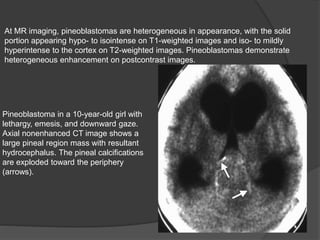

At MR imaging, pineoblastomas are heterogeneous in appearance, with the solid

portion appearing hypo- to isointense on T1-weighted images and iso- to mildly

hyperintense to the cortex on T2-weighted images. Pineoblastomas demonstrate

heterogeneous enhancement on postcontrast images.

Pineoblastoma in a 10-year-old girl with

lethargy, emesis, and downward gaze.

Axial nonenhanced CT image shows a

large pineal region mass with resultant

hydrocephalus. The pineal calcifications

are exploded toward the periphery

(arrows).